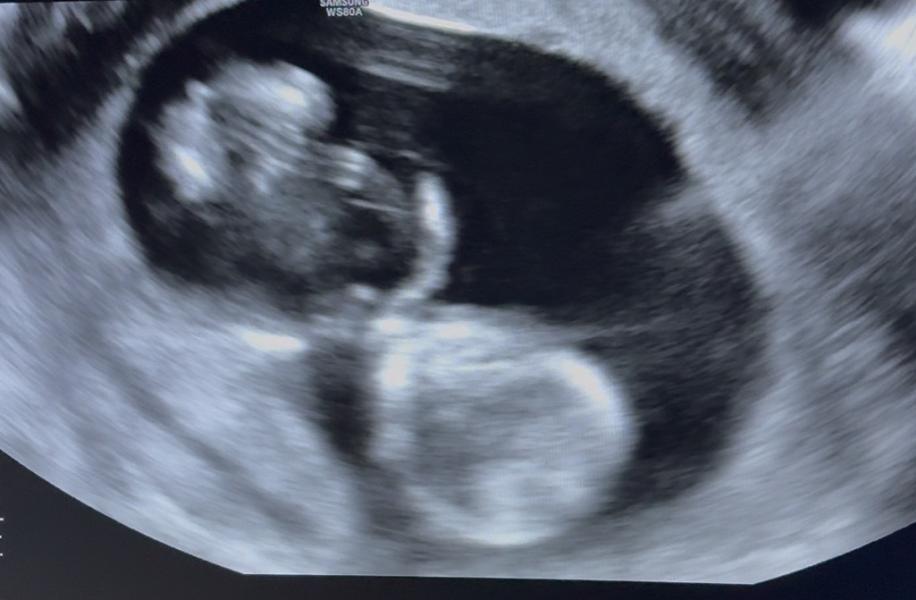

Единственная фотка, где,возможно, видно половой бугорок, но и та не с того ракурса 😄 как думаете, на кого похоже?)

Тут вообще непонятно, его видно но сверху, а надо сбоку смотреть (